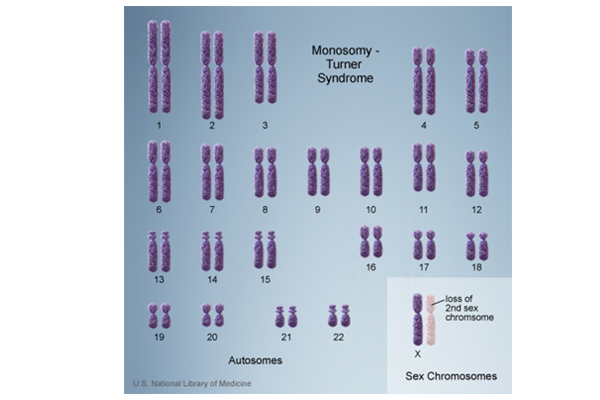

特纳综合征(Monosomy X)和妊娠丢失往往是相关的。特纳综合征是一种染色体疾病,其中女孩或女人只有一条完整的X染色体(因为一个人需要Y染色体才能成为男性,所...

自发流产是指在胚胎发育过程中,由于某种内部的或外部的原因引起妊娠自行终止的现象(不包括人工流产)。导致自发流产的原因很多,染色体异常是自发流产最常见原因。不孕不育...